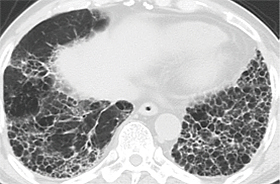

HRCTにおける特発性線維症の特徴

- 胸膜直下、肺底部優位

- 網状影

- 蜂巣肺(牽引性気管支拡張を伴うことも伴わないことも)

- 特発性肺線維症に合致しない所見をもたないことも